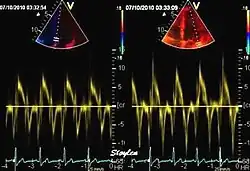

Pulsed tissue Doppler echocardiography

This has become a major echocardiographic tool for assessment of both systolic and diastolic ventricular function. However, as this is a spectral technique, it is important to realise that measurement of peak values is dependent on the width of the spectrum, which again is a function of gain setting.

Pulsed wave spectral tissue Doppler has become a universal tool that is part of the general echocardiographic examination. Like any other echocardiographic measurement, measures by tissue Doppler should be interpreted in the context of the whole examination. The velocity curves are in general taken from the base of the mitral annulus at the insertion of the mitral leaflets, in the septal and lateral points of the four chamber view, and eventually the anterior and inferior points of the two-chamber views. For the right ventricle it is customary to use the lateral point of the tricuspid annulus only. Averaging peak velocities from the septal and lateral point has become common, although it has been shown that averaging all four points mentioned above, gives significantly less variability[3]

The method measures annular velocities to and from the probe during the heart cycle.

Annular velocities summarize the longitudinal contraction of the ventricle during systole, and elongation during diastole. Peak velocities are commonly used.